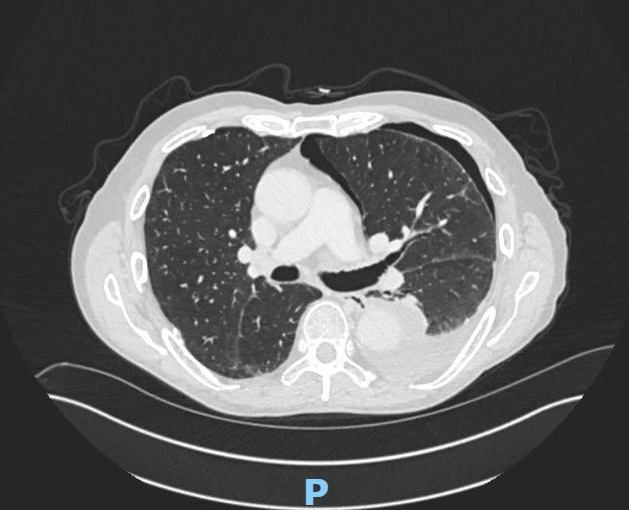

Secondary pneumothoraces can be the first presentation of pleural malignancies and may also complicate their course. They are often associated with prolonged air leaks, and cardiothoracic intervention can be required. https://bit.ly/3DEvPem.

Abstract Image